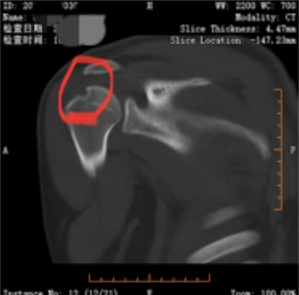

经朋友推荐,小欧来到该院骨二科就诊。通过详细查体及三维CT、核磁共振评估,医生明确诊断其合并Bankart损伤(肩关节盂唇前下方撕裂)和Hill-Sachs损伤(肱骨头后外侧骨折)——这正是导致肩膀反复“出走”的根源。

【凹陷骨折处】